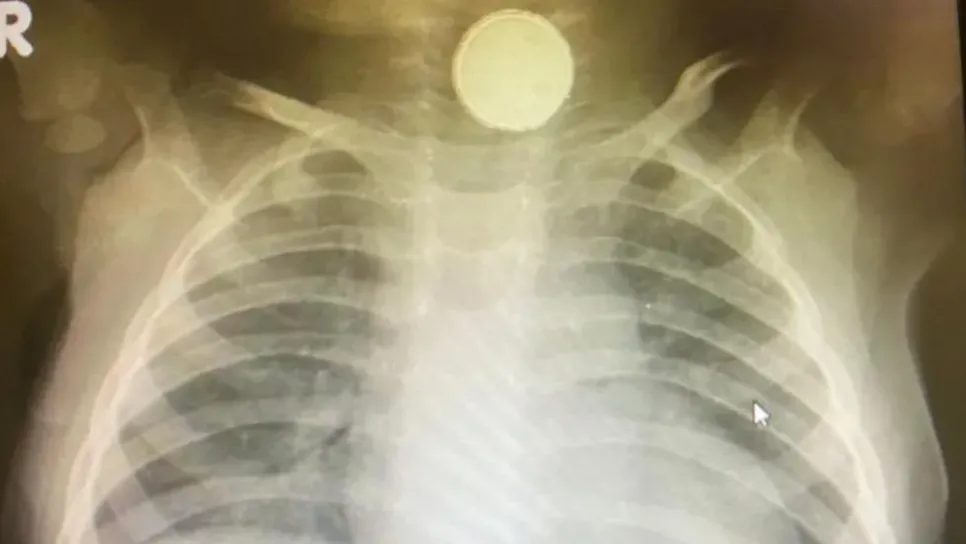

بينت فحوصات طبية أن بطارية ظلت عالقة في حلق رضيعة لمدة أربعة أشهر. واعتقد الأطباء في أول الأمر أن صوفيا غريس هيل كانت تعاني من التهاب اللوزتين قبل أن تكشف صور الأشعة عن بطارية صغيرة عالقة في المريء. وخضعت لعملية جراحية استغرقت ساعتين لإزالة البطارية، وهي الآن تتغذى بالسوائل فحسب. وتعتقد الطبيبة الجراحة أن الرضيعة بقيت على قيد الحياة، ربما لأن البطارية قديمة وخالية من الطاقة. ولاحظ والد الرضيعة مشكلة ابنته في يناير/ كانون الثاني من عام 2020، وعرضها على عدد من الممرضين، كما زارت الطبيب أكثر من مرة، وأخذت إلى المستشفى أيضا، بمنطقة سويندن في انجلترا. وكان متيقنا من أن ابنته تعاني من مشكلة، لأنها ل...